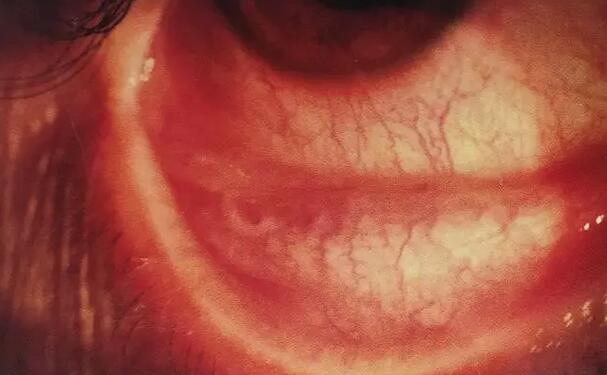

8月7日,刚完成白内障手术的邹大哥到厦门眼科中心漳州眼科医院复查,术后视力 良好。几个月前邹大哥在工地在干活时,工地上的水泥砂浆突然溅入他右眼,几个月来逐渐看不清近物,两眼不平衡,立体感差,上下楼梯老要踏空,干活不得劲,效率差,严重影响到我的日常生活和工作。

据了解,邹大哥曾在几家医院均被诊断为白内障,建议他等看不见时再手术。“还好,听说厦门眼科中心在漳州开了家分院,我在家人的陪同下到厦门眼科中心漳州眼科医院诊治。”门诊吴强主任发现其右眼视力0.1,眼内已有铁锈症,让厦门眼科中心的陈燕主任会诊,经院内世代的 设备检查,明确诊断后入院医治。陈燕主任为患者做了白内障超声乳化联合晶体植入,并通过玻璃体切割,清除眼内铁锈混浊的玻璃体,将眼球内2MM磁性异物取出,联合眼内光术,一*次性完成手术。

邹大哥手术非常 ,术后右眼视力0.8。“都怪我自己不重视,才让病情更严重。现在右眼能够清晰的看事物了,真的非常感谢陈燕主任和漳州眼科医院的医务人员精心医治护理,让我右眼重见光明”。